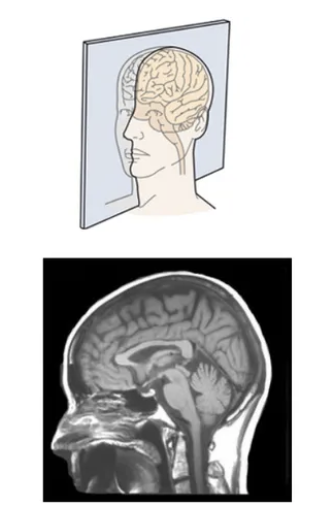

sagittal plane

<p></p>